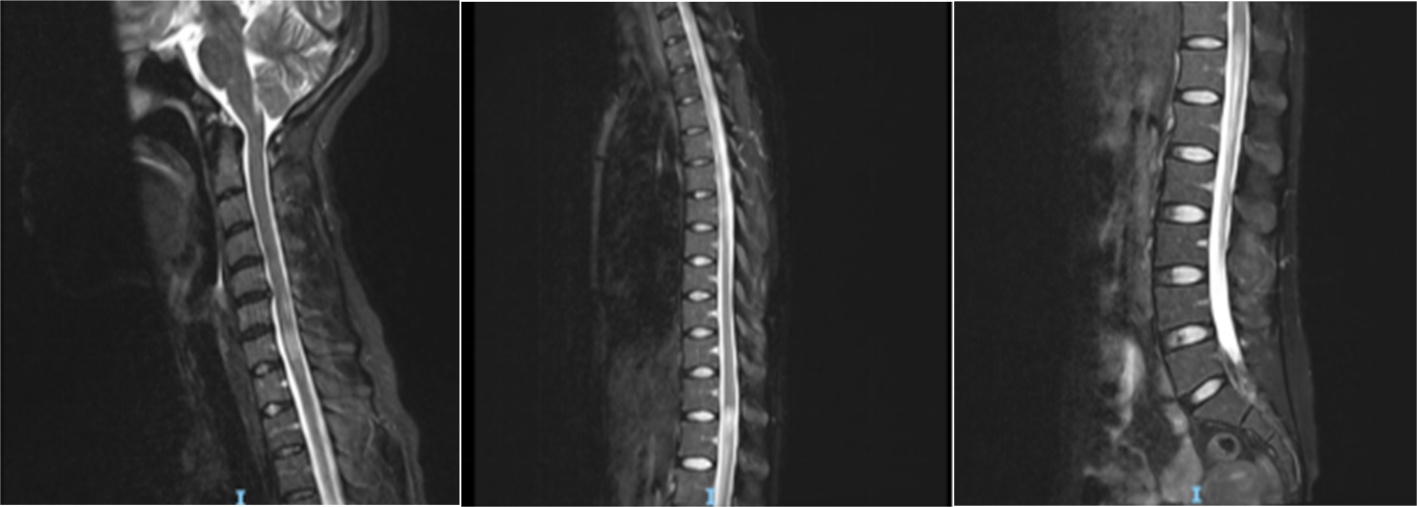

患者9月7日入住我院EICU,予以补液、护胃等对症治疗后症状未见明显好转,行腰椎穿刺术示:潘氏试验阳性,白细胞数19 × 106/L,蛋白定量0.85 g/L,提示蛋白细胞分离(见表1),考虑吉兰巴雷可能性大转入我院神经内科治疗。9月8日转入我院神经内科后予以泮托拉唑护胃、间苯三酚解痉,呃逆、呕吐症状较前稍改善,9月10日~9月14日予以丙种球蛋白20 mg ivbydrip Qd调节免疫治疗后呕吐、呃逆及双下肢乏力症状稍缓解。9月13日复查腰椎穿刺术示:细胞数正常,蛋白定量0.89 g/L,潘氏试验阳性(见表2)。完善头颅MRI + DWI示:腹侧丘脑、双侧视交叉、延髓背侧、右侧视神经周围多发异常信号,考虑脱髓鞘病变可能性大(见图1),颈胸腰椎增强MRI示:1. 颈胸椎脊髓内多发异常信号灶;2. 腰5、骶1层面椎管内占位,性质待定(见图2)。

Figure 2. MRI of the cervical, thoracic, and lumbar spine shows multiple abnormal signal foci within the cervical and thoracic spinal cord

2. 患者颈胸腰椎MRI示颈胸椎脊髓内多发异常信号灶

视神经脊髓炎是一种严重的炎性脱髓鞘性中枢神经系统自身免疫性疾病,其特征是视神经炎和纵向广泛的横向脊髓炎的反复发作[1]。视神经脊髓炎谱系疾病的核心临床综合征包括视神经炎引起的视力丧失,脊髓炎引起的脊髓综合征,后脑区病变引起的难治性恶心、呕吐和打嗝。因下丘脑损伤和大脑病变引起的其他临床综合征不太常见[2]。2021年发布的NMODS诊疗指南中指出,当AQP4-IgG阴性时,需要至少2项核心临床特征并满足下列全部条件:① 至少1项临床核心特征为ON、急性LETM或延髓最后区综合征;② 空间多发T2个或以上不同的临床核心特征;③ 满足MRI附加条件;④ 排除其他诊断时方可诊断NMODS [3]。本病例以极后区综合征及长节段性横贯性脊髓炎所致双下肢乏力为主要症状,影像学提示颈胸椎脊髓内多发异常信号灶,符合指南中AQP4-IgG阴性视神经脊髓炎的诊断标准,诊断视神经脊髓炎谱系疾病无误。